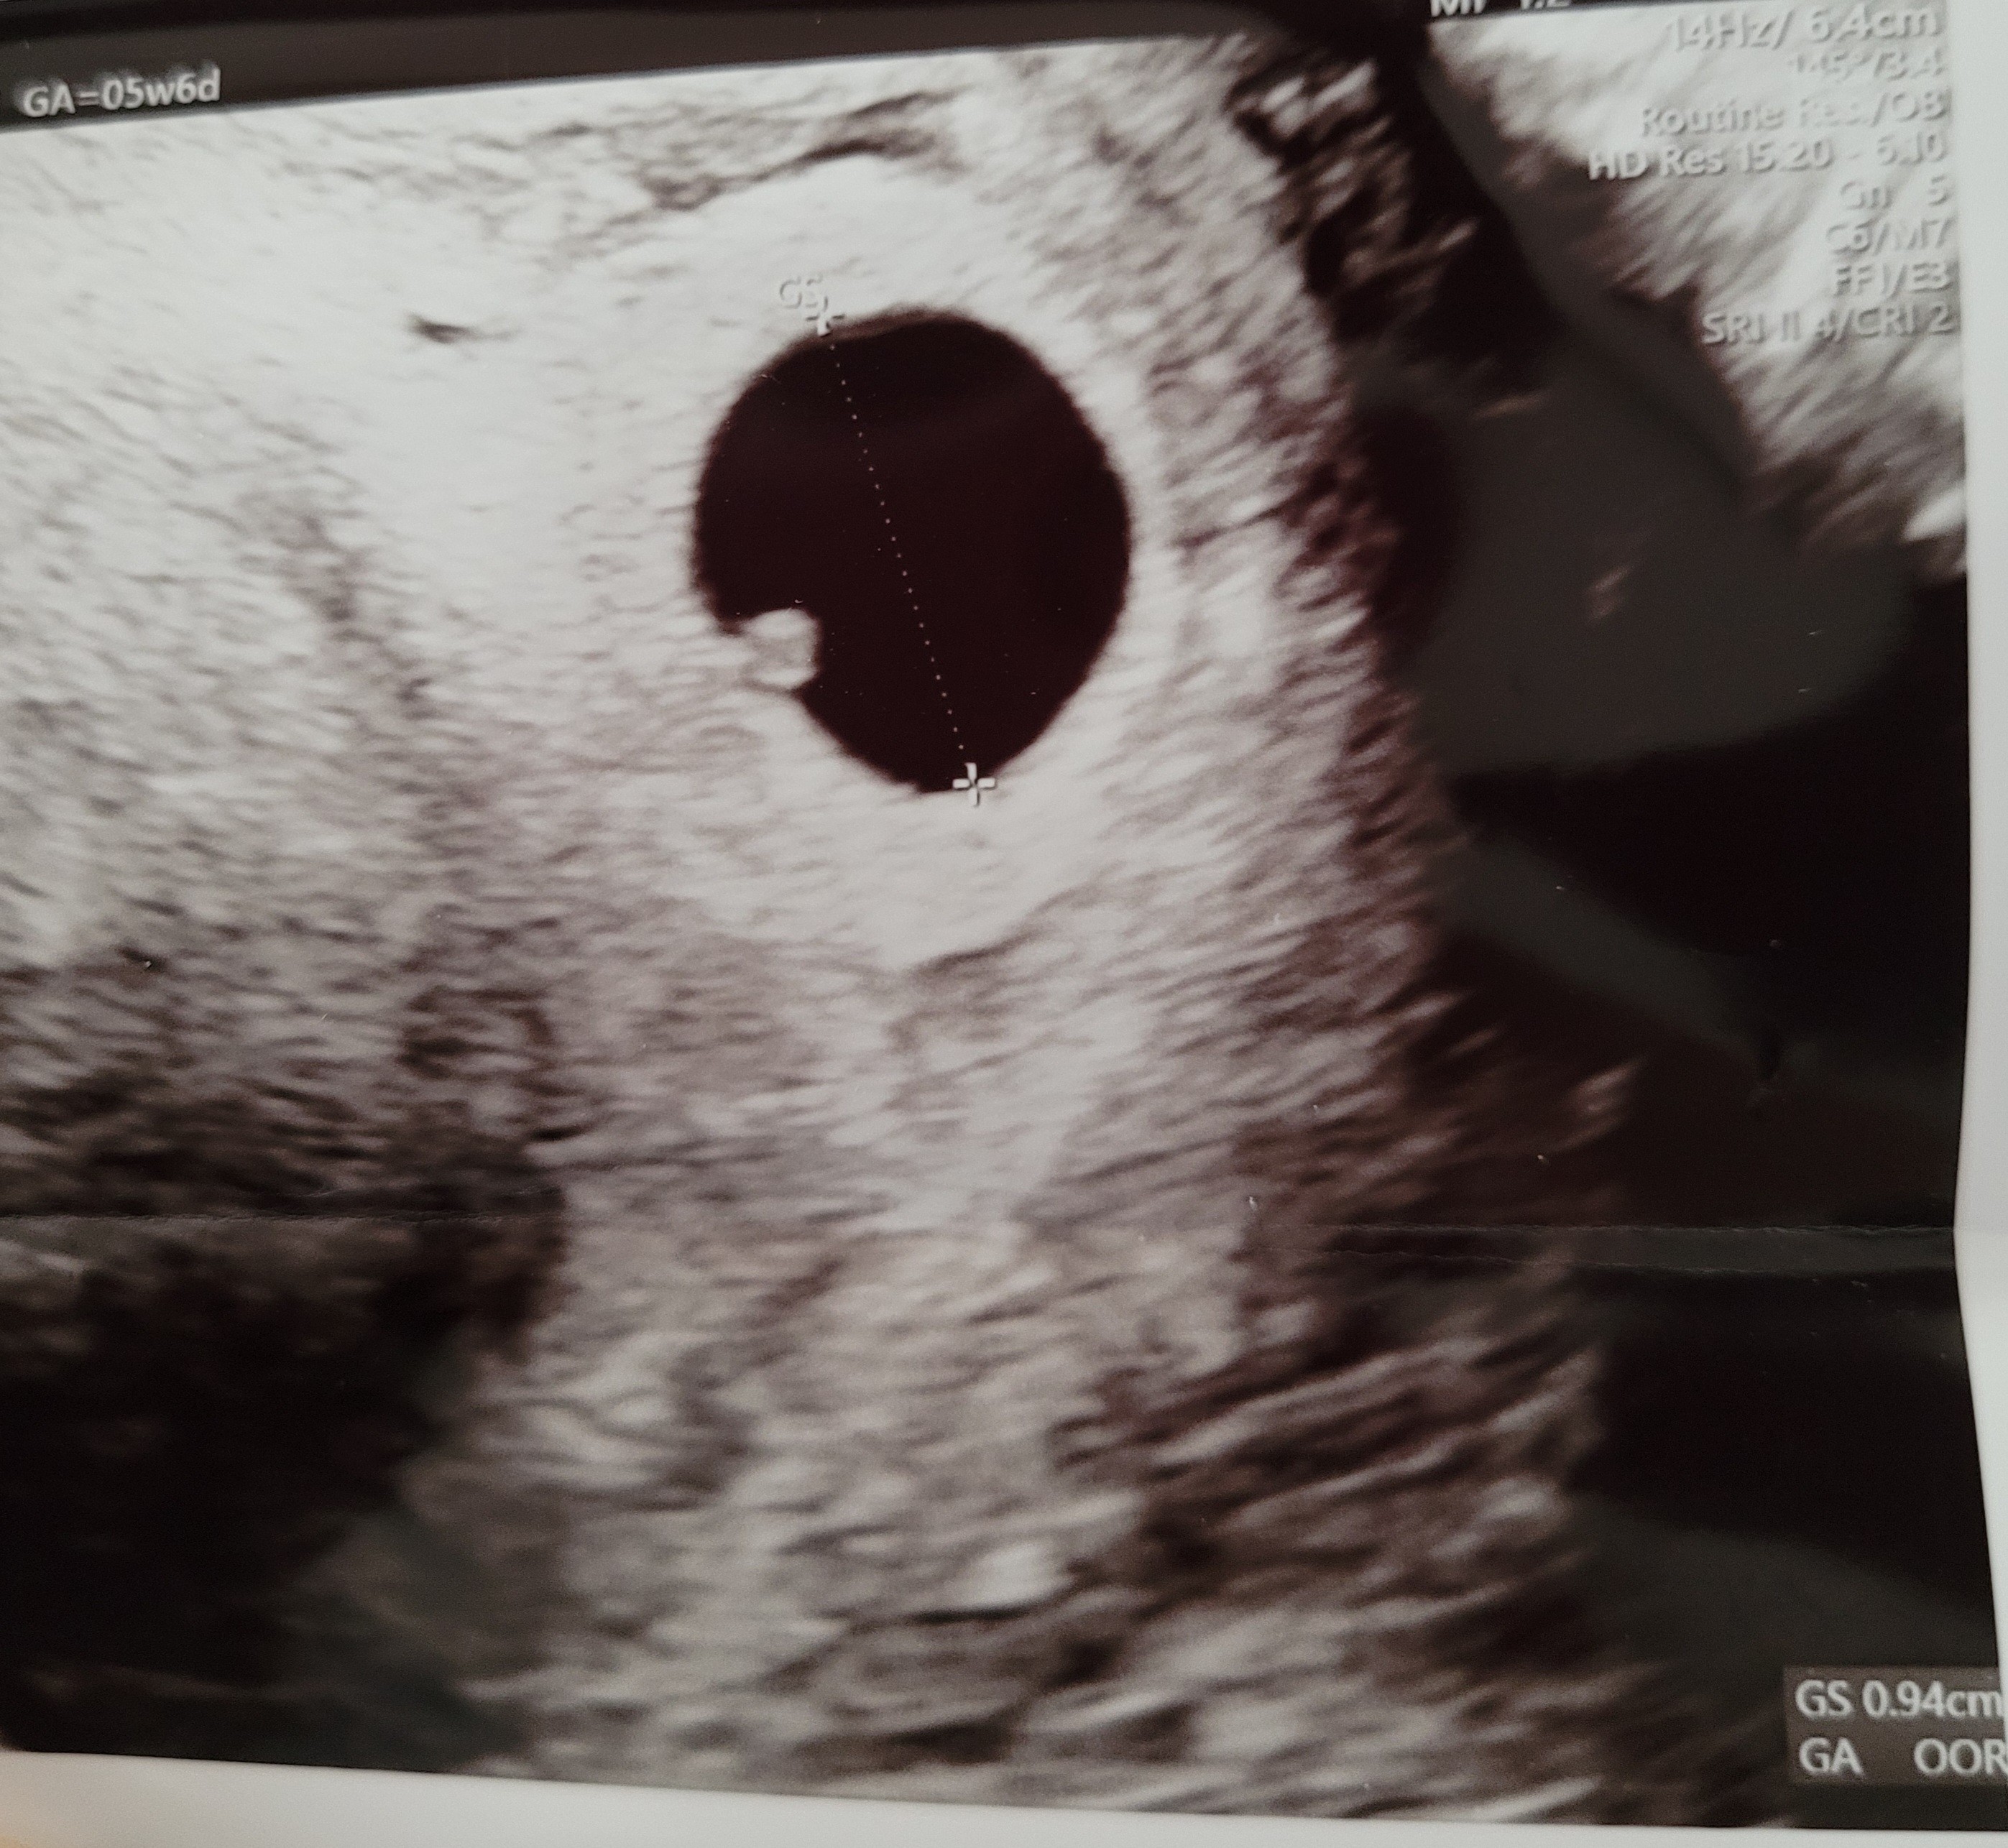

Witam wszystkich :) chciałabym zapytać odnośnie usg. Czy któraś z was też miała takie w 5t6d i mogłaby mi napisać co to za kółko przy lewej ścianie pęcherzyka ciążowego?

Załączniki

• 20230215_090209.jpg

20230215_090209.jpg

1,3 MB · Wyświetleń: 97